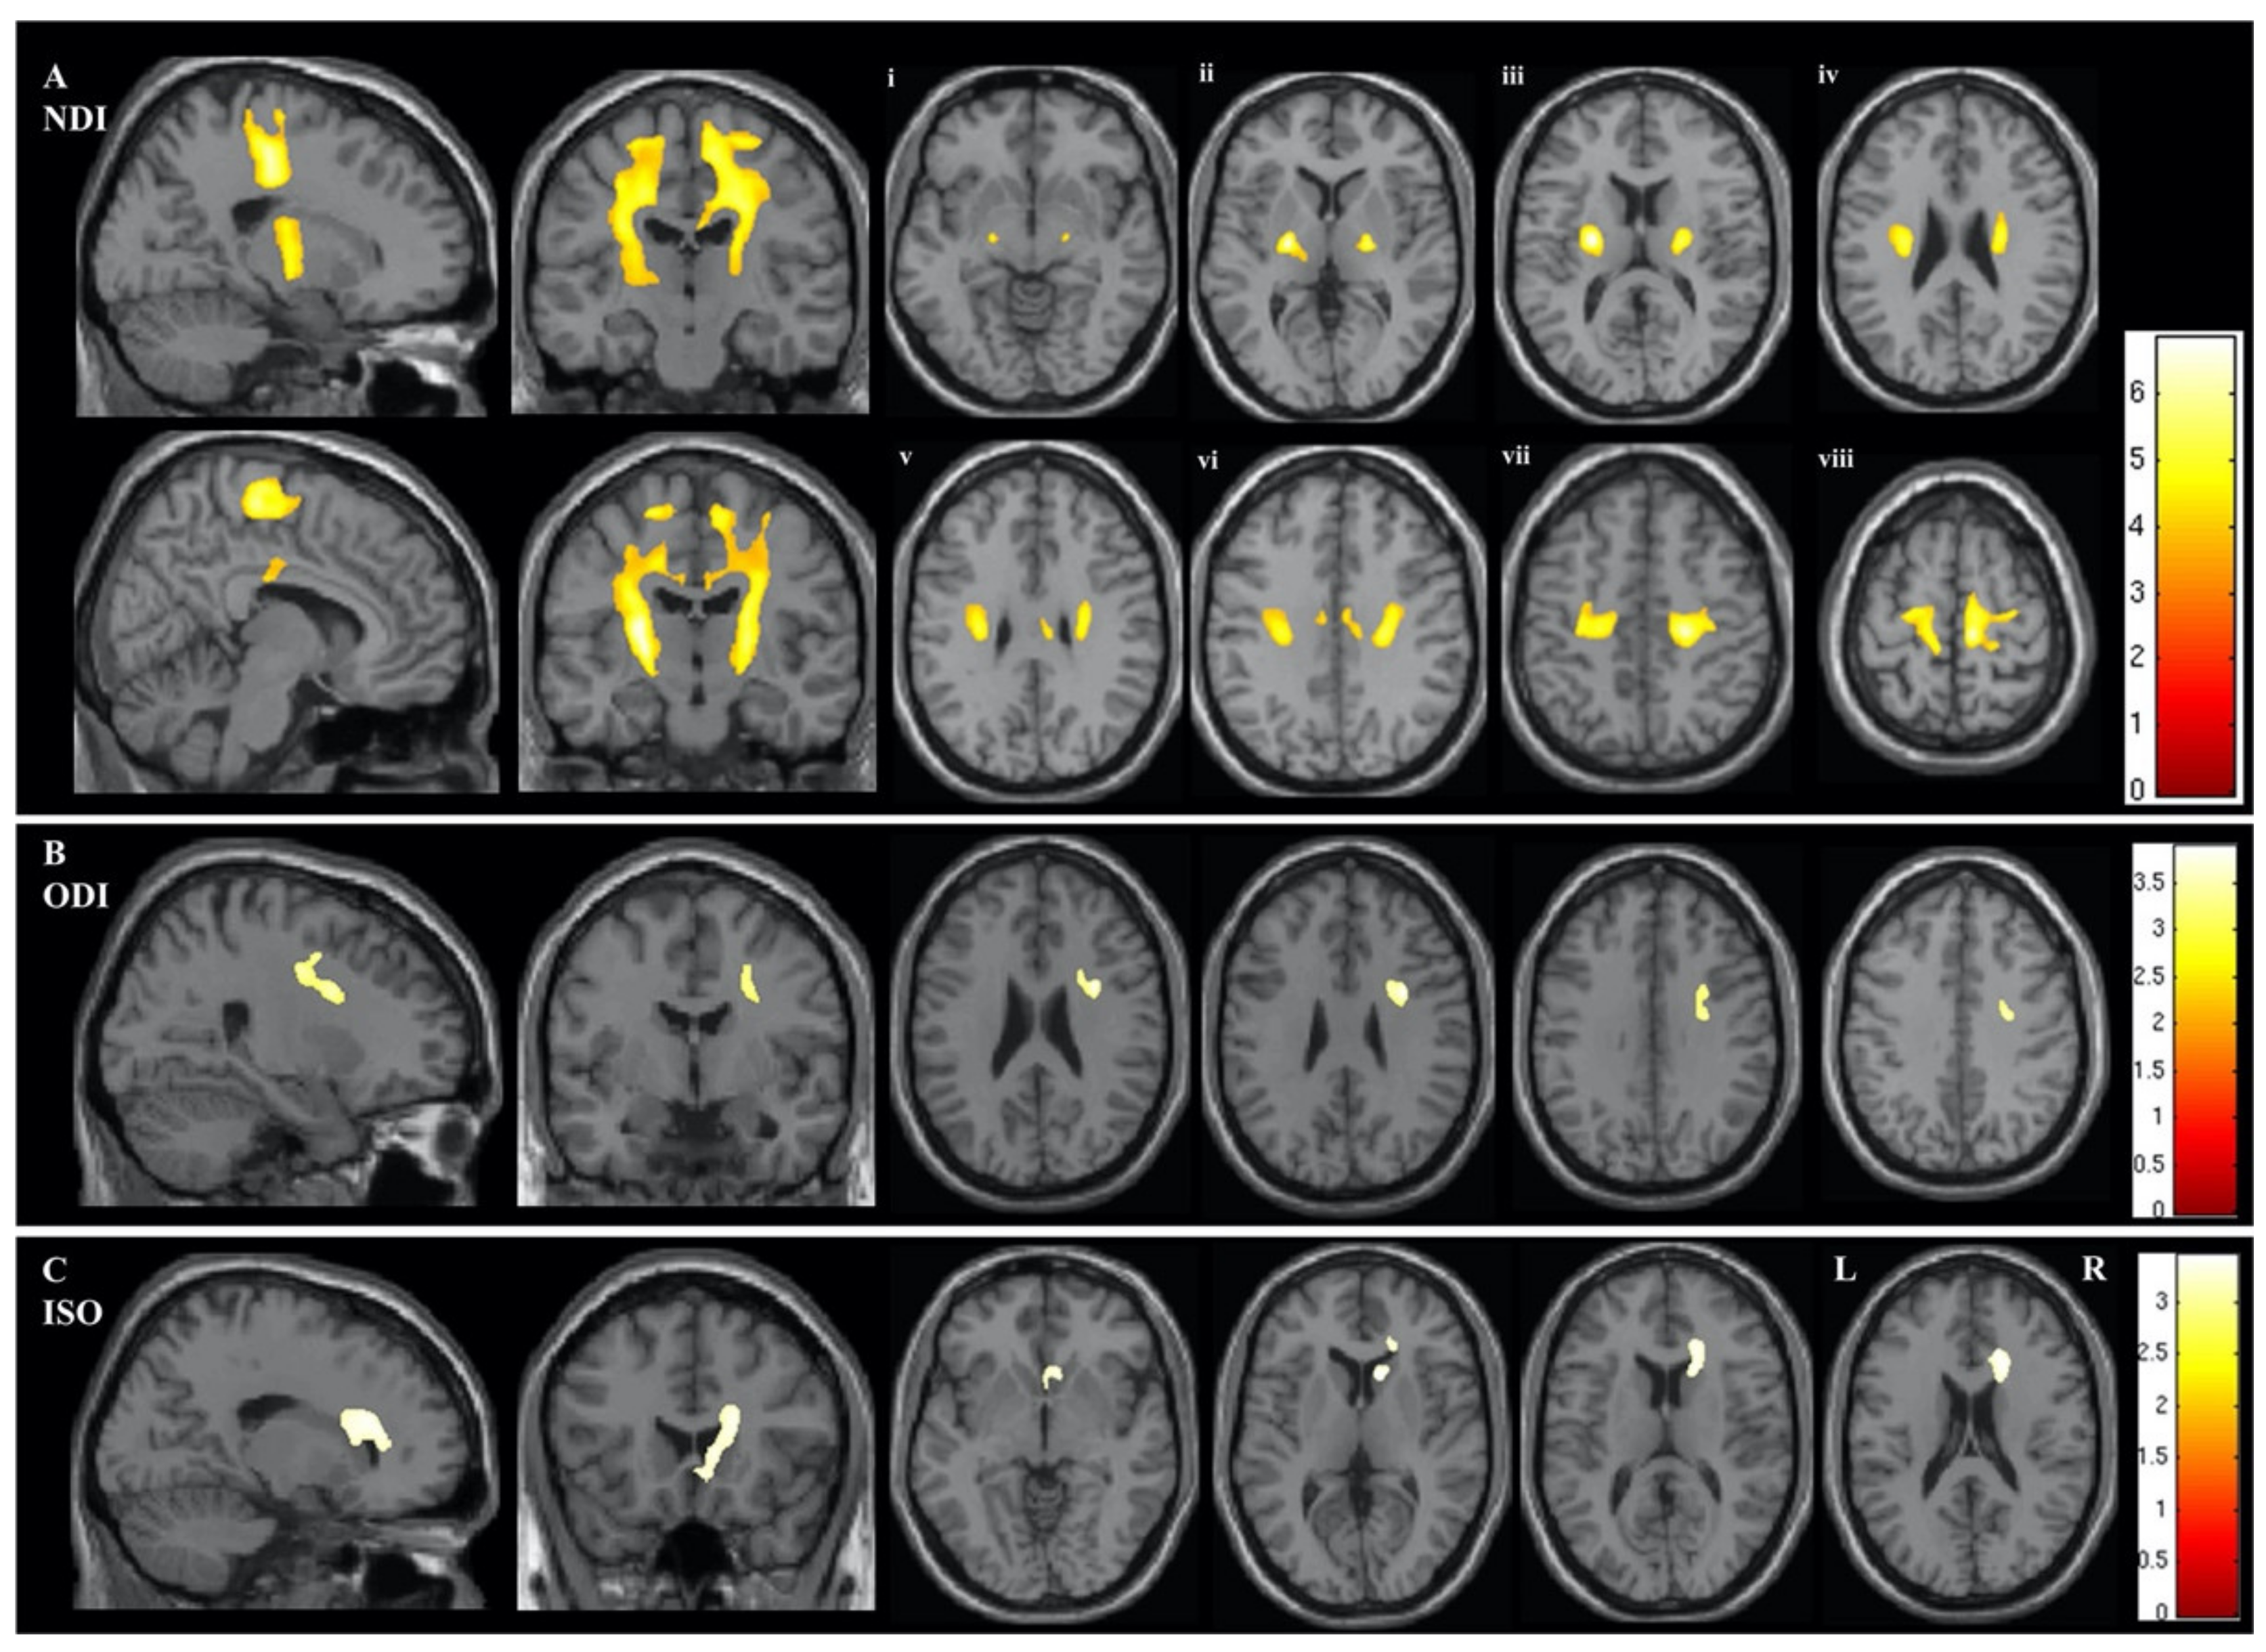

3.1.4. NODDI in AlzD

- Fu, X.; Shrestha, S.; Sun, M.; Wu, Q.; Luo, Y.; Zhang, X.; Yin, J.; Ni, H. Microstructural White Matter Alterations in Mild Cognitive Impairment and Alzheimer’s Disease: Study Based on Neurite Orientation Dispersion and Density Imaging (NODDI). Clin. Neuroradiol. 2020, 30, 569–579. [Google Scholar] [CrossRef] [PubMed]

- Wen, Q.; Mustafi, S.M.; Li, J.; Risacher, S.L.; Tallman, E.; Brown, S.A.; West, J.D.; Harezlak, J.; Farlow, M.R.; Unverzagt, F.W.; et al. White matter alterations in early-stage Alzheimer’s disease: A tract-specific study. Alzheimers Dement. (Amst) 2019, 11, 576–587. [Google Scholar] [CrossRef]

- Vogt, N.M.; Hunt, J.F.; Adluru, N.; Dean, D.C.; Johnson, S.C.; Asthana, S.; Yu, J.J.; Alexander, A.L.; Bendlin, B.B. Cortical Microstructural Alterations in Mild Cognitive Impairment and Alzheimer’s Disease Dementia. Cereb Cortex 2020, 30, 2948–2960. [Google Scholar] [CrossRef] [PubMed]

- Parker, T.D.; Slattery, C.F.; Zhang, J.; Nicholas, J.M.; Paterson, R.W.; Foulkes, A.J.M.; Malone, I.B.; Thomas, D.L.; Modat, M.; Cash, D.M.; et al. Cortical microstructure in young onset Alzheimer’s disease using neurite orientation dispersion and density imaging. Hum. Brain Mapp. 2018, 39, 3005–3017. [Google Scholar] [CrossRef]